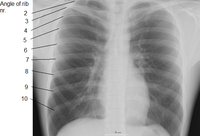

![]() القفص الصدري البشري. الأضلاع تتصل بالعمود الفقري، ومنه تنحني للأسفل وللأمام لتشكل قفصًا واقيًا حول القلب والرئتين. ويوجد في جسم الإنسان 24 ضلعًا، 12 ضلعًا في كل جانب. (المصدر: Gray's Anatomy of the Human Body, 20th ed. 1918) | |

Human ribs (shown in red). It consists of 24 ribs. Left and right of first rib to twelfth rib.